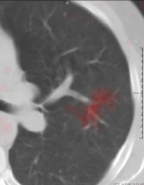

Muenzing et al. [2014] generated an uncertainty map by spatial interpolation of landmark-based quality estimates. On the contrary, our proposed system, which is trained on landmark locations, can be applied in all regions of the image. We showed this for two example images, see Fig. 5. It can be easily visualized that in the blue region, images are matched correctly. On the other hand, by tracking the vessels in the red region misalignment can be seen. Another note about the prediction is that there are no abrupt changes, and error varies smoothly from blue to yellow and then red, even though the error is predicted for each voxel independently.

Another example is given in Fig. 10(a-d). Although all landmarks indicate that the registration error is small in this slice, the quantitative results found several misregistered regions, which implies that few landmarks may not be sufficient to assess the registration quality of the whole image. In Fig. 10(e, f), it can be observed that the performance in the homogeneous area (left side of the images) is as good as the performance in the area with structure. The main reason of acceptable performance in the homogeneous area is that the training samples consist of landmarks as well as their neighborhood region, which can be homogeneous. Thus, the system is trained both for homogeneous regions and regions with structure.

Another example is given in Fig 10(g, h), where the proposed system is not able to predict the registration error correctly because of a shift in the slice direction.

Refer to caption

() Sample 1: IFsubscript𝐼𝐹{I}_{F}

(a) Sample 1: IM(𝐓b)subscript𝐼𝑀superscript𝐓b{I}_{M}(\bf{T^{\mathrm{b}}})

(b) Magnification of (a)

(c) Magnification of (b)

(d) Sample 2: IFsubscript𝐼𝐹{I}_{F}

(e) Sample 2: IM(𝐓b)subscript𝐼𝑀superscript𝐓b{I}_{M}(\bf{T^{\mathrm{b}}})

(f) Sample 3: IFsubscript𝐼𝐹{I}_{F}

(g) Sample 3: IM(𝐓b)subscript𝐼𝑀superscript𝐓b{I}_{M}(\bf{T^{\mathrm{b}}})

Figure 10: Several samples from the SPREAD dataset. The left column shows the fixed image with the ground truth registration error overlaid in color. The right column shows the moving image after registration with the registration error predicted by the proposed method overlaid in color.